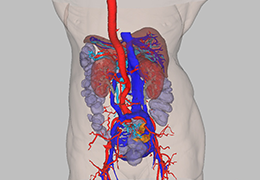

Designed for surgeons, Pro Surgical 3D makes it easy to view patient scans quickly. Pro Surgical 3D facilitates the optimal 3D treatment and assessment workflows based on X-ray CT and MRI scans – and best of all, it’s FREE!

Everyone – including surgeons, patients and their loved ones – benefits from being better informed by the wealth of information buried within CT and MRI scans. Pro Surgical 3D gives surgeons more information to develop optimal treatment plans for patients. It also helps patients and their support group better understand their medical condition and proposed treatment options.

High-quality and fast 3D reconstruction and 3D rendering

Performs 3D reconstruction and volume rendering.

Side-by-side comparative assessment for pre- and post-operative scans.